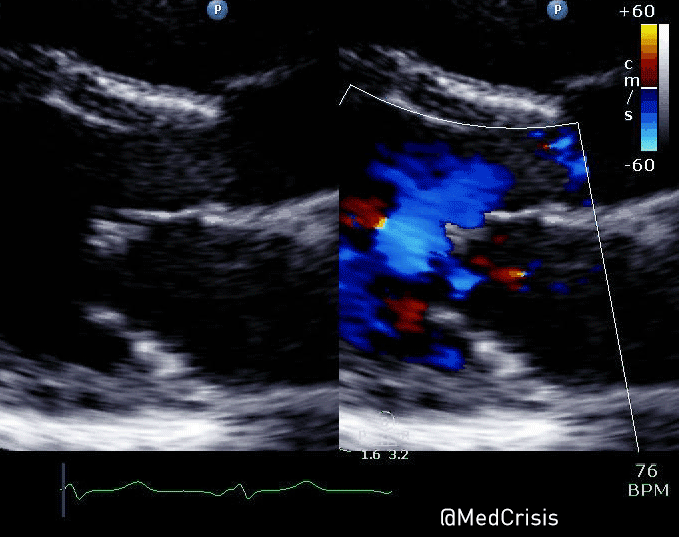

A parasternal long axis view reveals the posterior mitral valve leaflet is tethered. The basal posterolateral wall is hypokinetic.

A close up of the valve with colour Doppler demonstrates mitral regurgitation.

An apical 4-chamber (zoomed in) shows the mitral regurgitation is significant.